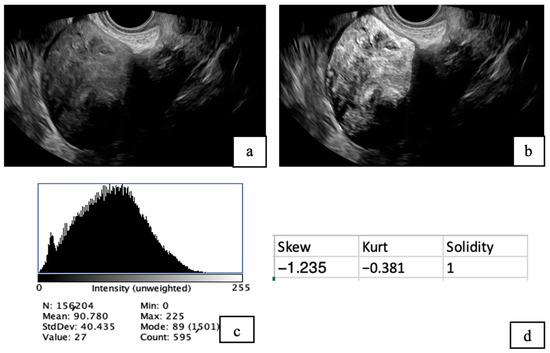

• Fibroid ultrasound images were analyzed using Fiji (ImageJ) version 20250529-2217 [28] (Schindelin et al., 2012) following a standardized protocol. Images were first opened in Fiji and converted to 8-bit grayscale for uniformity. Contrast was adjusted to optimize visibility of the fibroid structures. Segmentation was performed by manually delineating regions of interest (ROIs) encompassing the fibroids using selection tools. A histogram was utilized to obtain mean intensity, standard deviation (SD), minimum, and maximum values. Other quantitative measurements were obtained, including skewness, solidity, and kurtosis (Figure 1).

Figure 1. TVS images of uterine fibroids before (a) and after analysis using Fiji software (b). The post-analysis image highlights the presence of tiny cystic areas within the fibroid. A histogram (c) was generated to evaluate pixel intensity distribution, and additional quantitative analysis (d) was conducted to assess tissue characteristics, including skewness, solidity, and kurtosis.